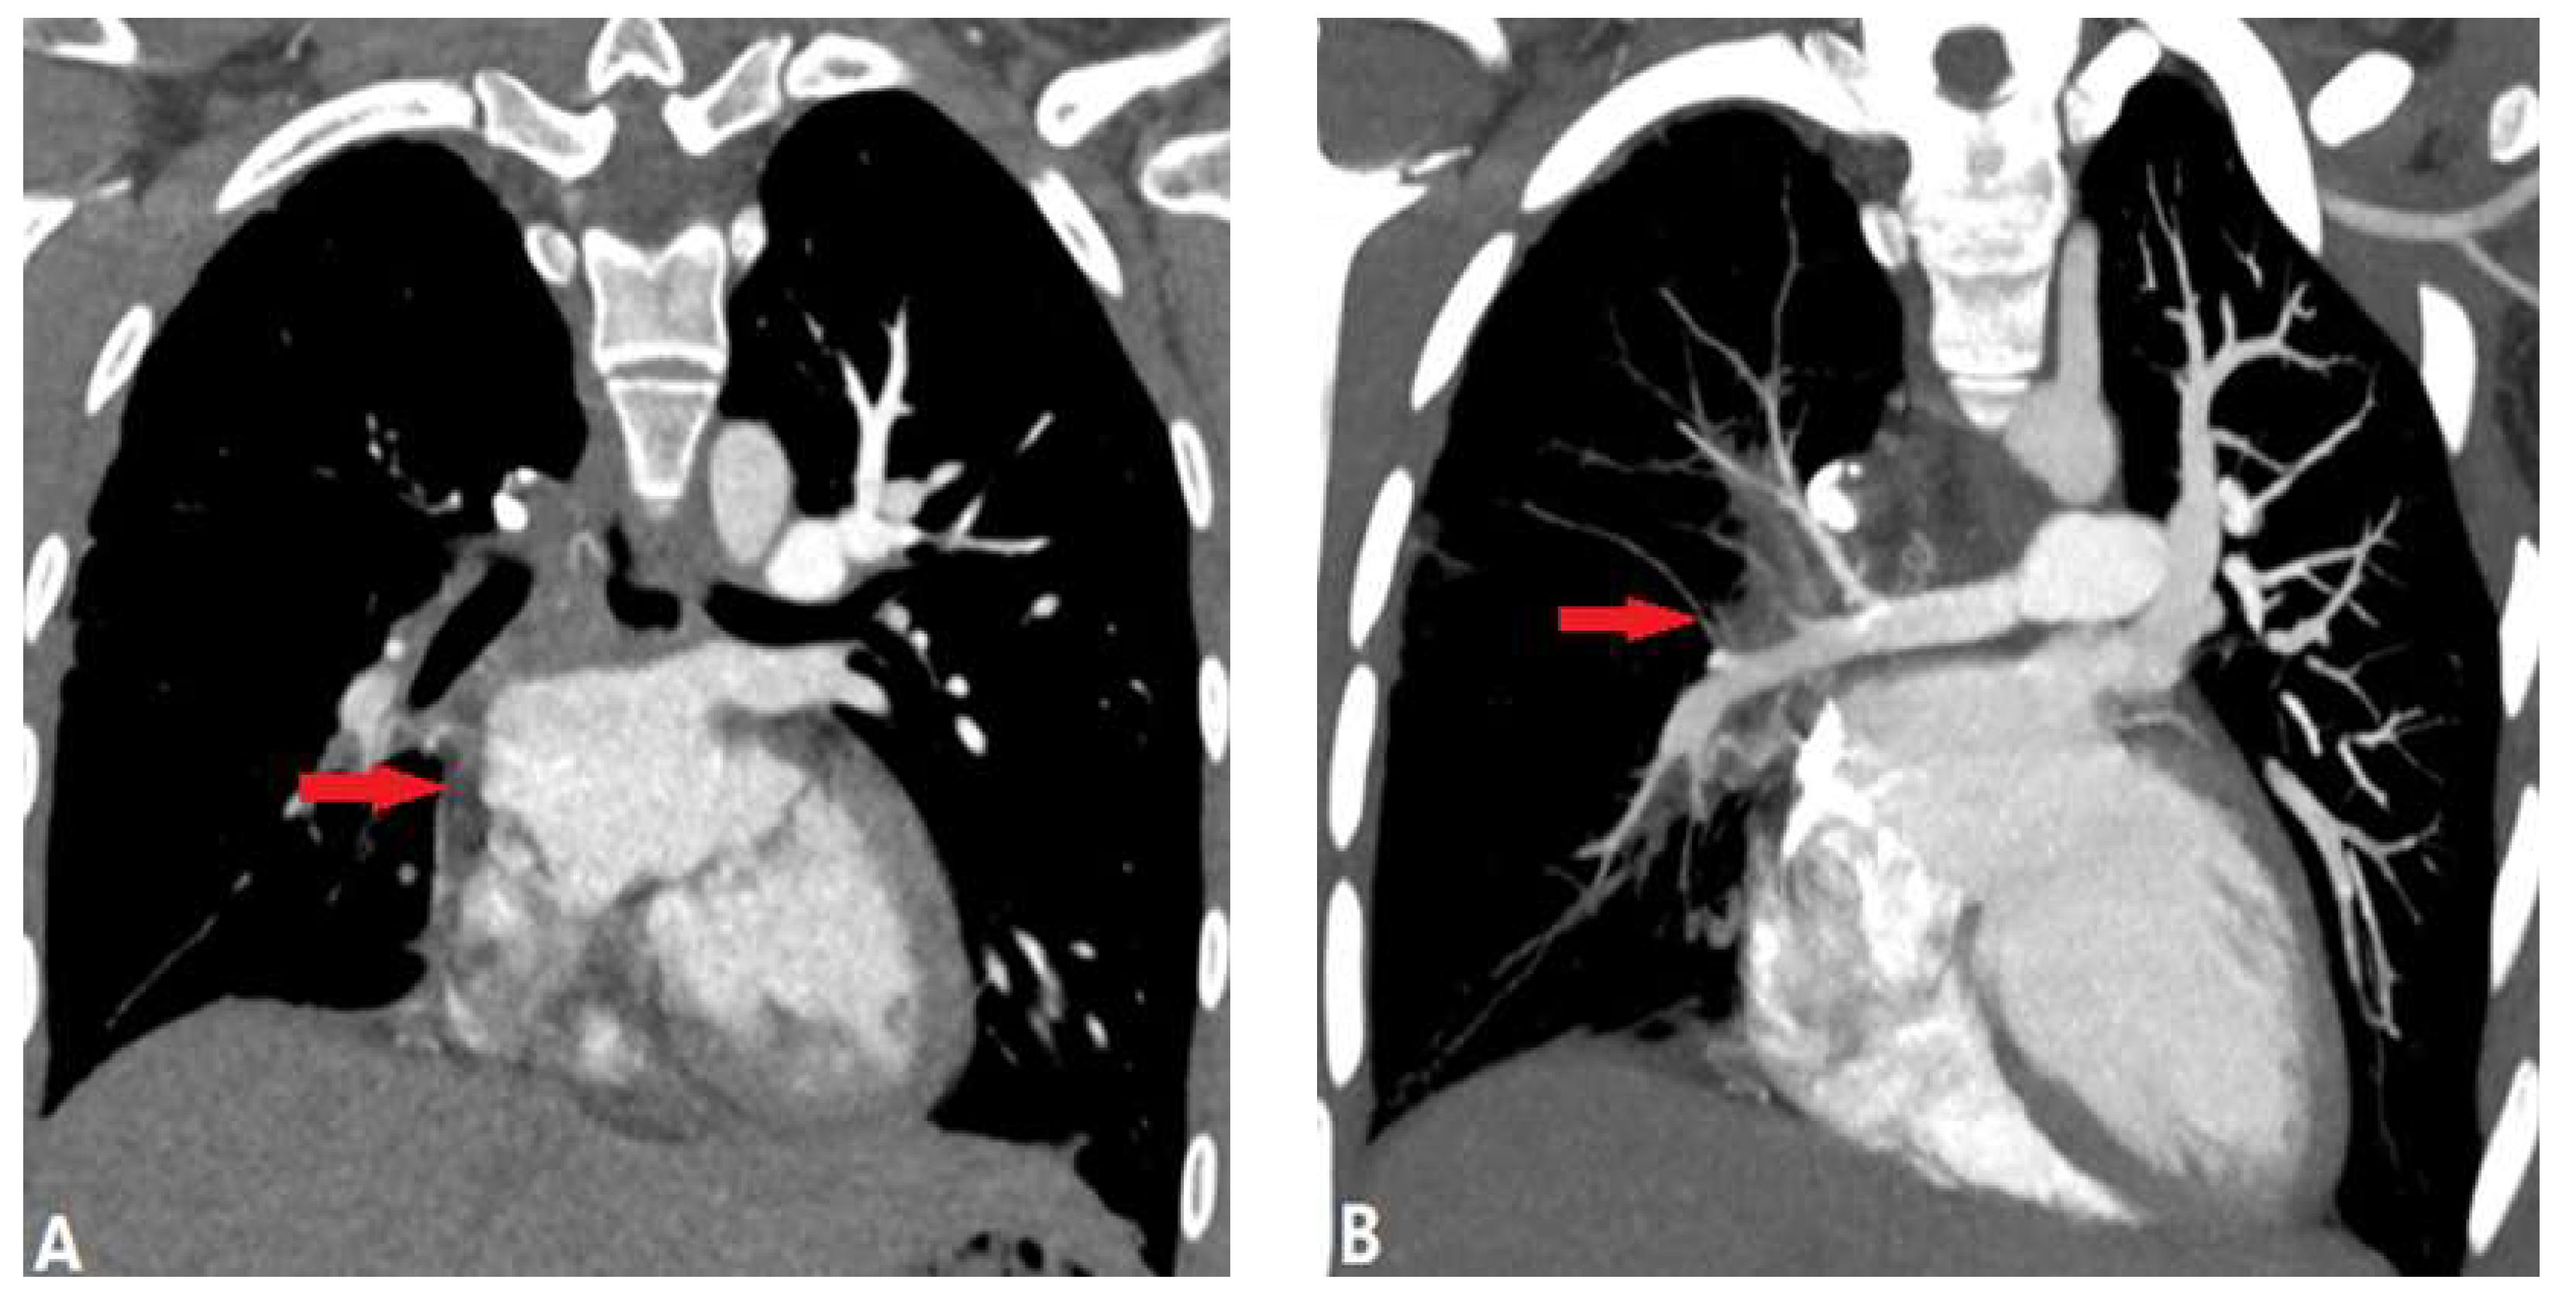

3.2.1.1. Takayasu Arteritis (TA)

3.2.1.2. Behçet Disease (BD)